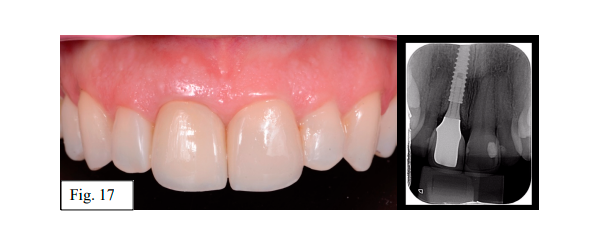

A paciente TAC, 39 anos, sexo feminino, procurou clínica privada com história de trauma bucal e posterior soltura da coroa do dente 11 (Fig. 1). Após avaliação clínica e tomográfica, foi diagnosticado fratura radicular. Dessa forma, seguiu-se com o planejamento para instalação de implante imediato com planejamento virtual e impressão de guia cirúrgica para instalação guiada com kit de Cirurgia Guiada da Implacil (Fig. 2).

O orifício de acesso palatino foi vedado com camada teflon e coberto com resina composta após tratamento padrão para obter adesão de resinas em cerâmica. A Fig. 17 demonstra o resultado protético obtido e a radiografia periapical após a conclusão.